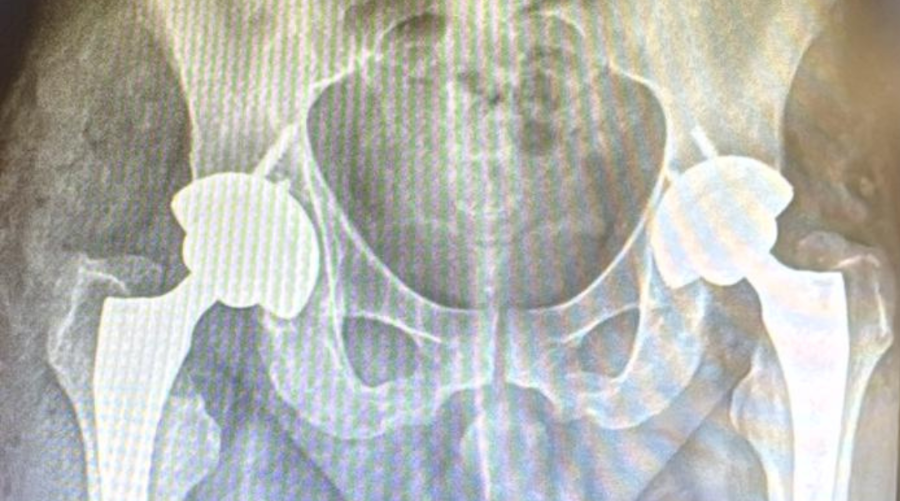

O Hospital Ouro Branco (HOB) realizou, de forma inédita, duas artroplastias totais de quadril em tempo único para o tratamento de osteonecrose bilateral das cabeças femorais. O procedimento foi executado no mesmo ato operatório, evitando cirurgias e internações em momentos distintos, o que representa um avanço técnico relevante para a ortopedia regional e para a instituição.

A artroplastia total de quadril é um procedimento cirúrgico indicado em casos de comprometimento avançado da articulação. A técnica consiste na substituição da articulação do quadril por próteses artificiais, com o objetivo de reduzir a do e restaurar a mobilidade do paciente.

Em grandes centros, esse tipo de procedimento geralmente exige a atuação simultânea de duas equipes médicas. No HOB, ambas as substituições articulares foram realizadas pela mesma equipe, com tempo total de 2 horas e 30 minutos.

Entre os principais destaques técnicos está o tempo cirúrgico otimizado, de aproximadamente 150 minutos, fator considerado determinante para a segurança anestésica e para a estabilidade clínica do paciente. Outro ponto relevante foi a realização de um procedimento de alta complexidade em um hospital de média complexidade do interior, sem suporte de UTI, viabilizada por planejamento rigoroso e execução precisa, assegurando uma recuperação estável e precoce.